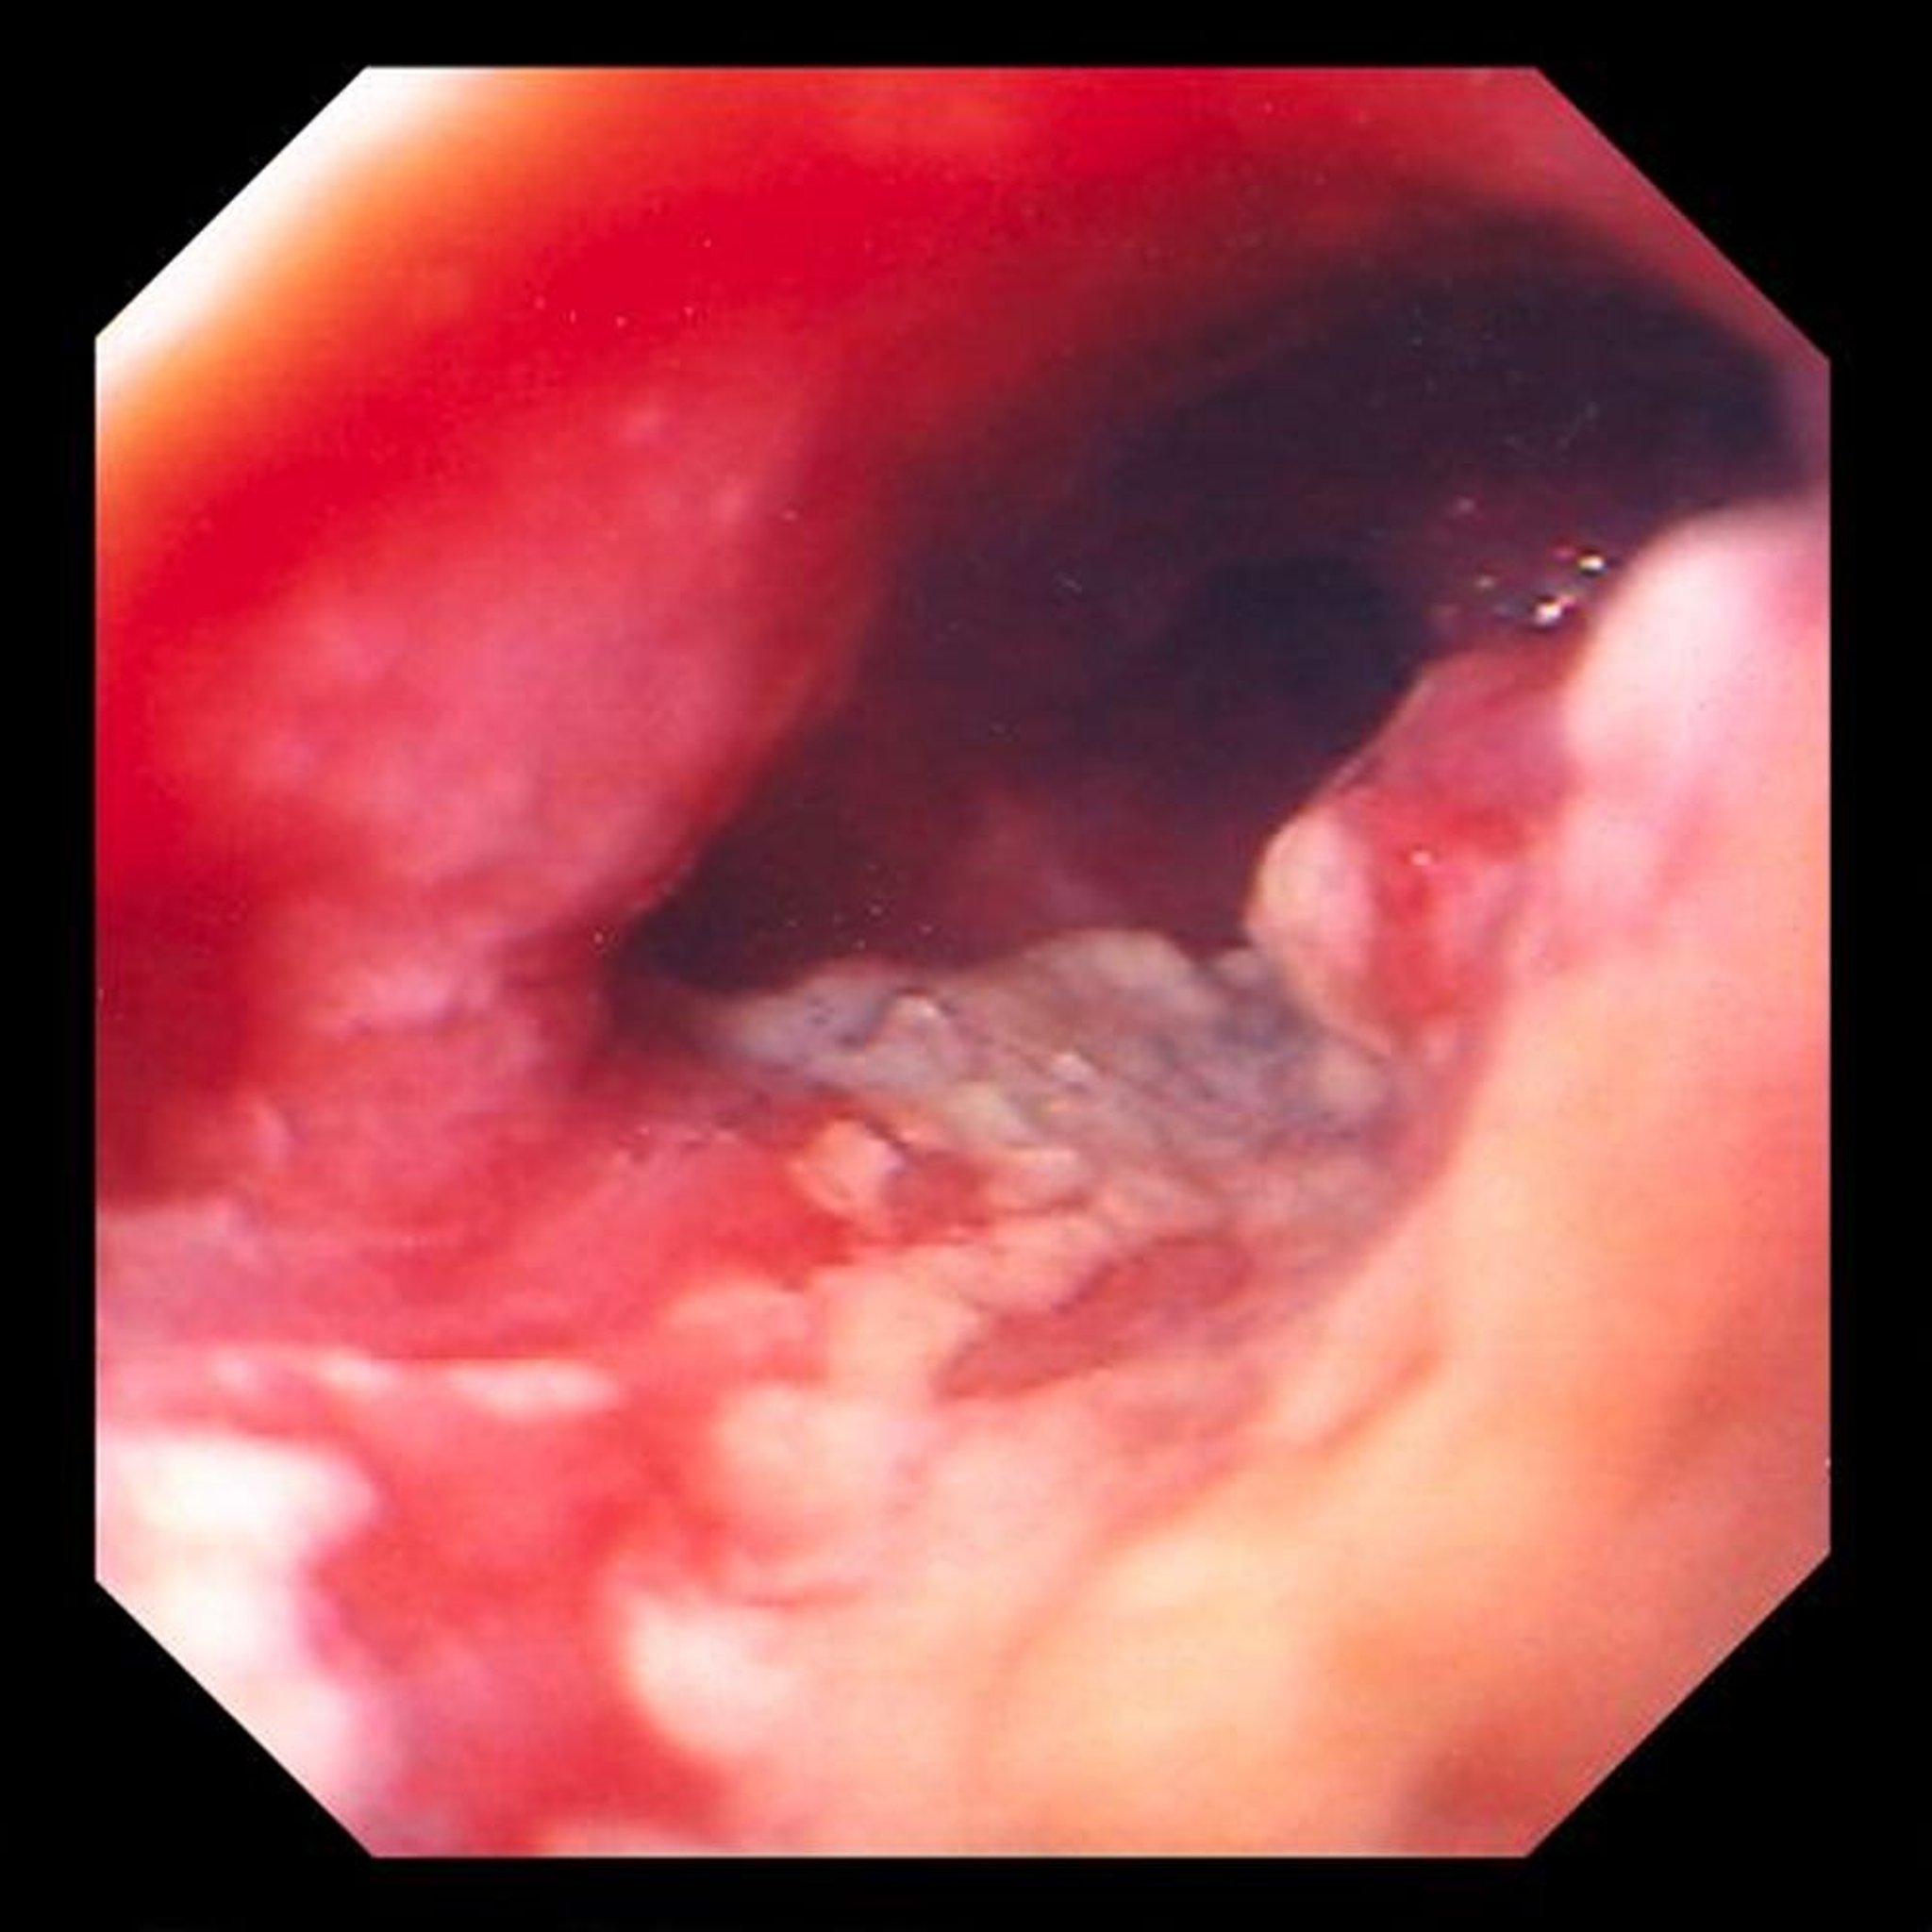

Adenocarcinoma of the Esophagus

This image shows an ulcerated, constricting tumor located in the distal esophagus, which is highly suggestive of an adenocarcinoma arising from metaplastic columnar changes (Barrett esophagus).

Image provided by David M. Martin, MD.